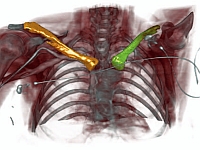

Antonio Pepe, Richard Schussnig, Jianning Li, Christina Gsaxner, Dieter Schmalstieg, Jan Egger:

| Shape reconstruction from imaging volumes is a recurring need in medical image analysis. Common workflows start with a segmentation step, followed by careful post-processing and, finally, ad hoc meshing algorithms. As this sequence can be time-consuming, neural networks are trained to reconstruct shapes through template deformation. These networks deliver state-of-the-art results without manual intervention, but, so far, they have primarily been evaluated on anatomical shapes with little topological variety between individuals. In contrast, other works favor learning implicit shape models, which have multiple benefits for meshing and visualization. Our work follows this direction by introducing deep medial voxels, a semi-implicit representation that faithfully approximates the topological skeleton from imaging volumes and eventually leads to shape reconstruction via convolution surfaces. Our reconstruction technique shows potential for both visualization and computer simulations. |